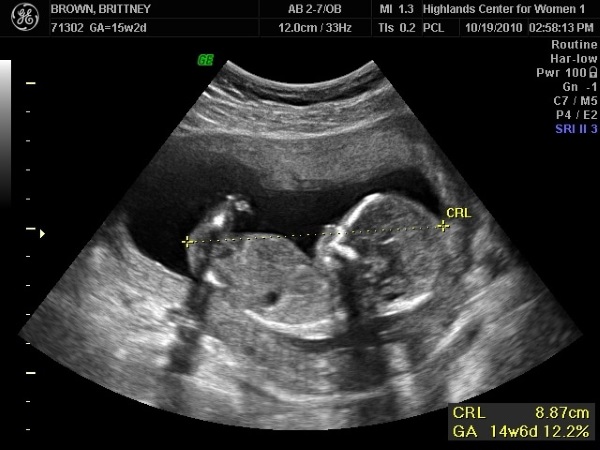

| Фото на УЗИ | Что можно увидеть на ультразвуковом исследовании. | На УЗИ можно четко рассмотреть контуры тела плода, его конечности, голову. Часто можно увидеть, как ребенок двигается, сосет палец, переворачивается. В некоторых случаях уже можно определить пол ребенка, хотя это не всегда возможно с высокой точностью на этом сроке. |

УЗИ и визуализация: На УЗИ в 15 недель можно увидеть, как плод активно двигается, хотя мама этого может еще не чувствовать. На этом этапе УЗИ может показать пол ребенка, если он находится в удобном положении. Также можно заметить, как формируются его конечности и черты лица, что делает это исследование особенно захватывающим для будущих родителей.

УЗИ на данном сроке позволяет увидеть, как формируются основные органы и системы. Плод уже достигает длины около 10 см и весит примерно 70 граммов. На экране можно разглядеть его маленькие ручки и ножки, а также сердцебиение, что вызывает у родителей сильные эмоции. Женщины часто делятся своими впечатлениями о том, как важно видеть своего малыша на экране, и как это укрепляет связь с ним. В целом, 15-я неделя — это время надежды и ожидания, когда будущие родители начинают осознавать чудо новой жизни.

Пол малыша определяется уже в момент образования эмбриона, однако половые органы начинают формироваться только к 13 неделе. К началу второго триместра заканчивается дифференциация первичных половых признаков. Несмотря на то, что у мальчиков на этом сроке уже начинает вырабатываться тестостерон, пол на УЗИ выявить сложно.

Однако опытный специалист сможет определить пол будущего наследника с помощью современной аппаратуры. Гинекологи выявляют этот момент за счет измерения угла между половым бугорком и спиной ребенка. У мальчиков половой бугорок образует угол больше 30 градусов, у девочек – меньше.

Если женщине повезет попасть на 3D-УЗИ, половую принадлежность можно определить почти со 100% вероятностью. Но даже в этом случае необходимо, чтобы ребенок занял «удобное» для определения положение.

Что видно на УЗИ в 15 недель беременности?

Гинеколог пальпирует матку через переднюю брюшную стенку, чтобы определить ее расположение относительно пупка. Также специалист прослушает сердцебиение плода. Если у вас 15 неделя беременности, узнать пол ребенка возможно с помощью УЗИ: половые органы ребенка полностью сформированы и хорошо визуализируются.